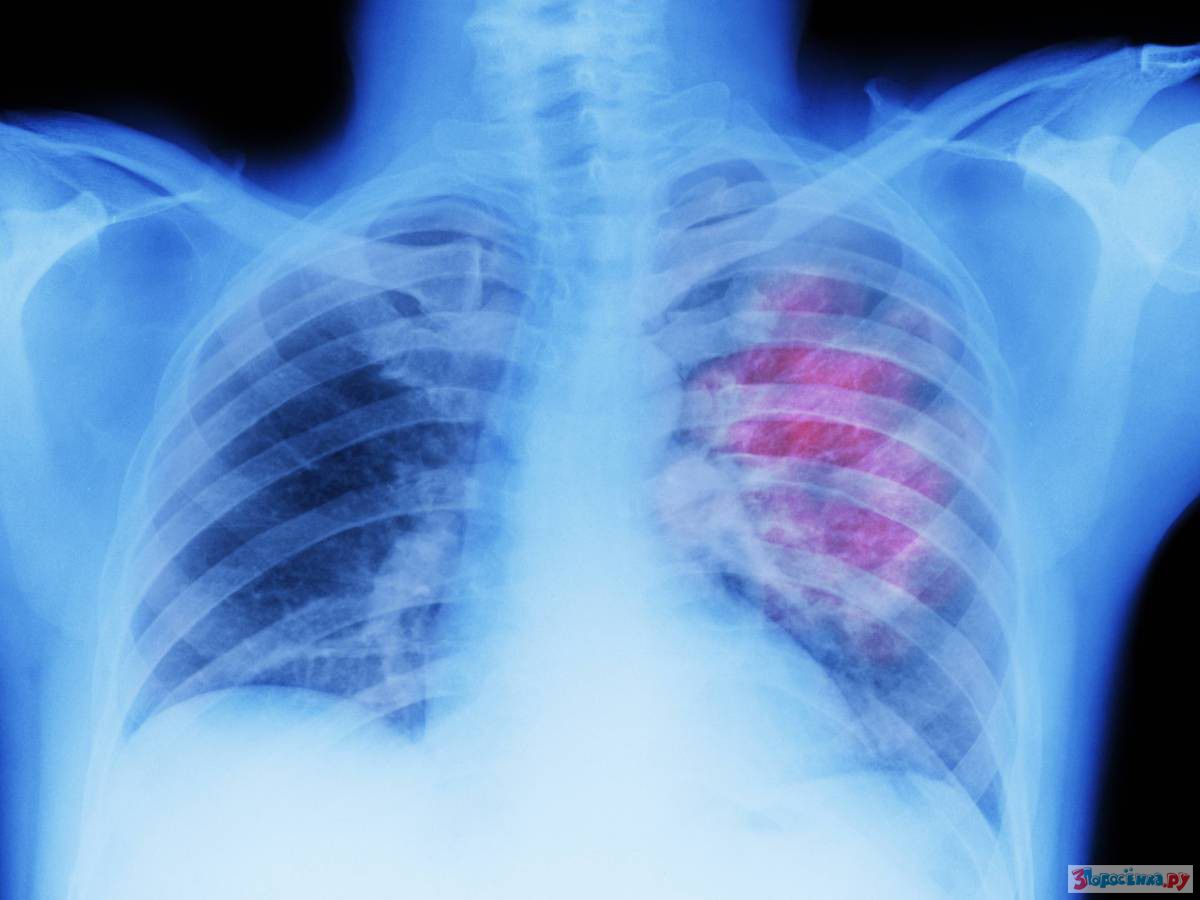

3 дня спустя восстанавливается дыхание

Через три дня в легких восстанавливается реснитчатый эпителий. Курение уничтожает микроскопические реснички, очищающие дыхательные пути. К счастью, эти реснички могут восстанавливаться.

Через две недели ослабевает кашель

Кашель начинает исчезать через две недели, после того как вы бросили курить. Он не исчезает сразу, так как вашим легким нужно время на выведение скопившихся в них вредных веществ. Как только вы бросаете курить ваше тело начинает восстанавливаться и очищаться.